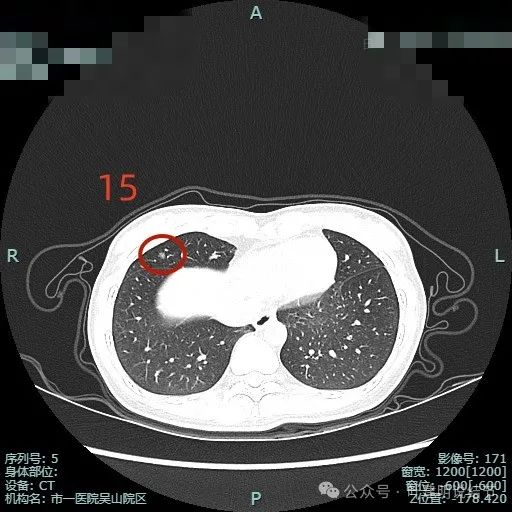

病灶15:右中叶磨玻璃结节,密度不太纯,边缘毛糙,整体轮廓较清,考虑原位癌或微浸润性腺癌可能性大。